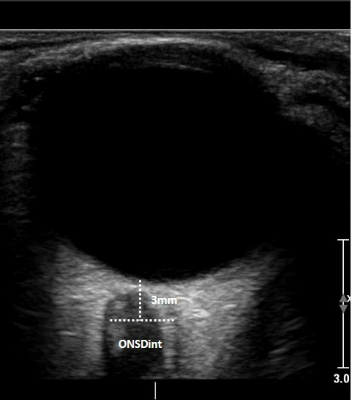

Bild: Optikusnervenscheiden-Durchmesser-Sonografie, © DEGUM/Michael Ertl

Beim ONSD-Ultraschall wird ein passender Schallkopf sanft auf das geschlossene Augenlid aufgesetzt. Die Untersuchung macht sich zunutze, dass sich Veränderungen in der Regel an der Hülle des Sehnervs zeigen, wenn der Druck im Schädelinneren steigt. Für die Betroffenen bedeutet das: keine Strahlenbelastung, keine Schmerzen, kein Eingriff. Bislang wurde ein erhöhter Hirndruck meist mit computertomografischen oder magnetresonanztomografischen Aufnahmen (CT oder MRT) oder durch eine invasive Liquordruckmessung über eine Lumbalpunktion festgestellt. Diese Verfahren liefern zwar sehr genaue Ergebnisse, sind jedoch zeitaufwändig, belastend oder nicht überall sofort verfügbar. „Die Optikusnervenscheiden-Sonografie bietet hier eine wertvolle, patientenschonende Ergänzung, insbesondere in Notfallsituationen oder wenn eine invasive Messung nicht möglich ist“, erklärt Ertl. „Und auch in Notfallsituationen, in denen eine aufwändige oder invasive Untersuchung nicht sofort möglich ist, liefert der Ultraschall schnell eine verlässliche Einschätzung“, so Ertl. Das Verfahren eignet sich nicht nur für akute neurologische Notfälle, sondern auch für die Verlaufsbeobachtung – etwa nach Kopfverletzungen, bei Hirnblutungen oder nach einer Wiederbelebung.